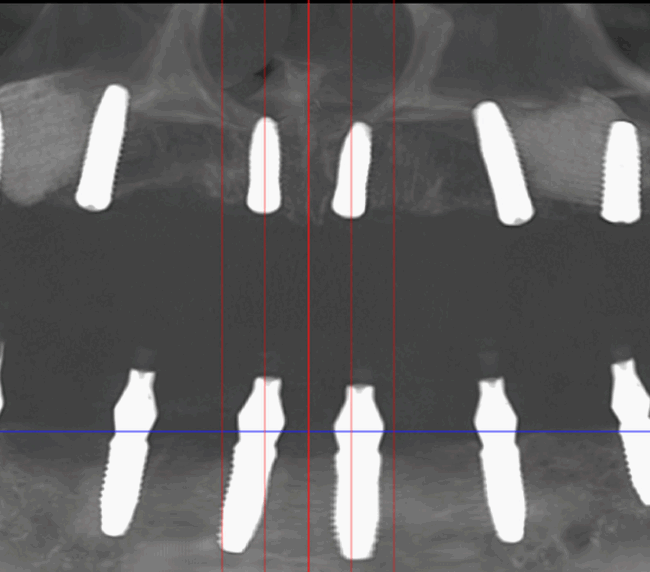

Caz 1